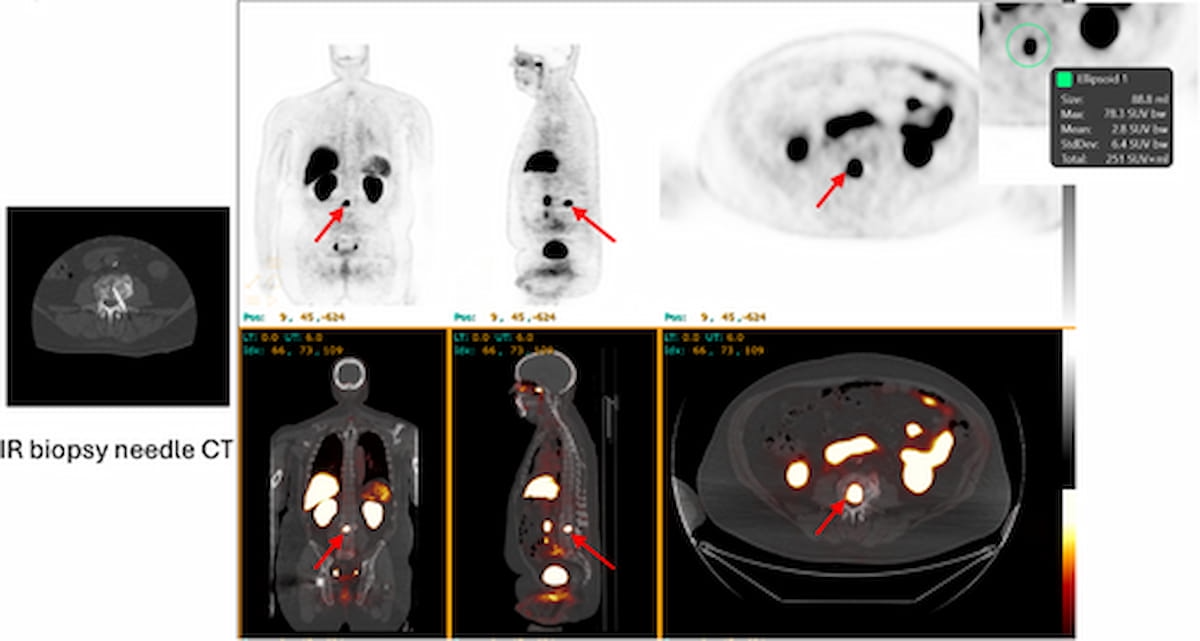

With initial suspicion of metastatic prostate cancer on conventional imaging, one can see 18F-piflufolastat PET/CT detection of a lesion in the L3 vertebral body for a patient receiving concomitant leuprolide and enzalutamide. (Images courtesy of The Prostate.)